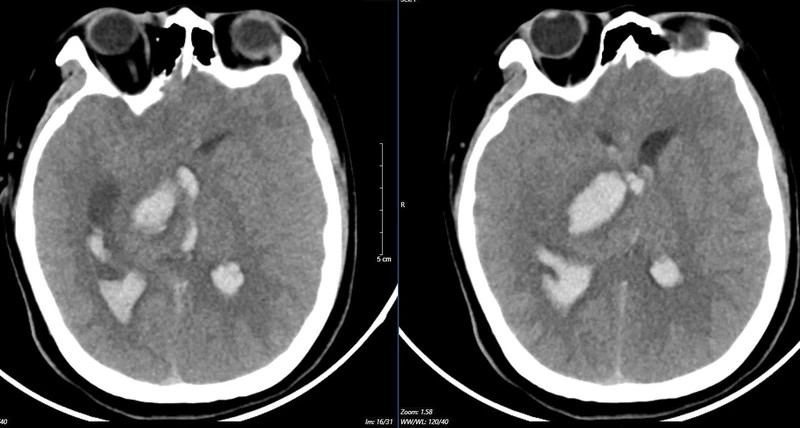

Kết quả chụp MSCT mạch não cho thấy chảy máu não thuỳ đỉnh phải, chảy máu não thất do vỡ AVM ( điểm Spetzler Martin 2 điểm). Bệnh nhân đã được phẫu thuật lấy máu tụ và khối dị dạng. Tuy được điều trị tích cực nhưng di chứng để lại vô cùng nặng nề. Sau một tháng điều trị, bệnh nhân chưa nhận thức được, liệt hoàn toàn nửa người trái…

Hình ảnh chụp MSCT mạch não: Chảy máu não thuỳ đỉnh phải, chảy máu não thất do vỡ AVM ( điểm Spetzler Martin 2 điểm) của bệnh nhân nữ, 29 tuổi. |

Nữ bệnh nhân 29 tuổi, tiền sử khoẻ mạnh. Bệnh nhân đến viện vì đột ngột đau đầu, tê tay, nôn nhiều vật vã. Tại bệnh viện tỉnh, bệnh nhân được chẩn đoán chảy máu não, các bác sĩ đã đặt ống nội khí quản thở máy rồi chuyển tuyến lên Trung tâm Đột quỵ, Bệnh viện Bạch Mai trong tình trạng ý thức hôn mê, Glasgow 6 điểm, thở máy, đồng tử bên phải giãn 4mm, tụt huyết áp, duy trì vận mạch.